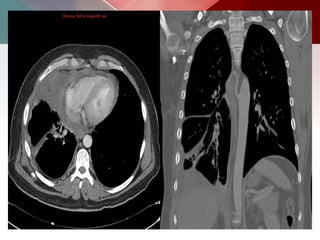

a)Squamous cell

 (SCC) is one of the non-small cell carcinomas of the

 Squamous cell carcinoma accounts for ~30-35% of all

 Macroscopically these tumors tend to be off-white in

 They invade the surrounding lung parenchyma and can

 Larger tumors have a tendency to undergo central

 The more central lesions may appear as a bulky hilum,

 Lobar collapse may be seen due to obstruction of a

mass is present, this is known as the Golden S sign.

or speculated mass.